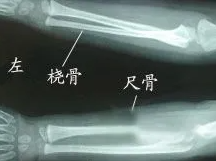

先天性尺桡骨融合是一种较为罕见的先天性骨发育畸形,主要表现为桡骨和尺骨的近端相互融合,而远端融合则极为罕见。这种畸形导致前臂固定在一定角度上,出现旋前畸形。

该病症的主要典型症状包括患侧前肢转动限制、肘关节伸直度不正常、前臂畸形以及生活障碍等。此外,患者还可能出现患侧肢体细弱、肘部疼痛、活动受限等其他症状。

5. 加强定期检查:定期体检和X光检查可以早期发现尺桡骨融合的迹象,及时采取措施预防进一步恶化。家长应加强对孩子的注意,一旦发现活动不正常或前臂旋转功能障碍等症状,应及时带孩子到正规医院就诊。